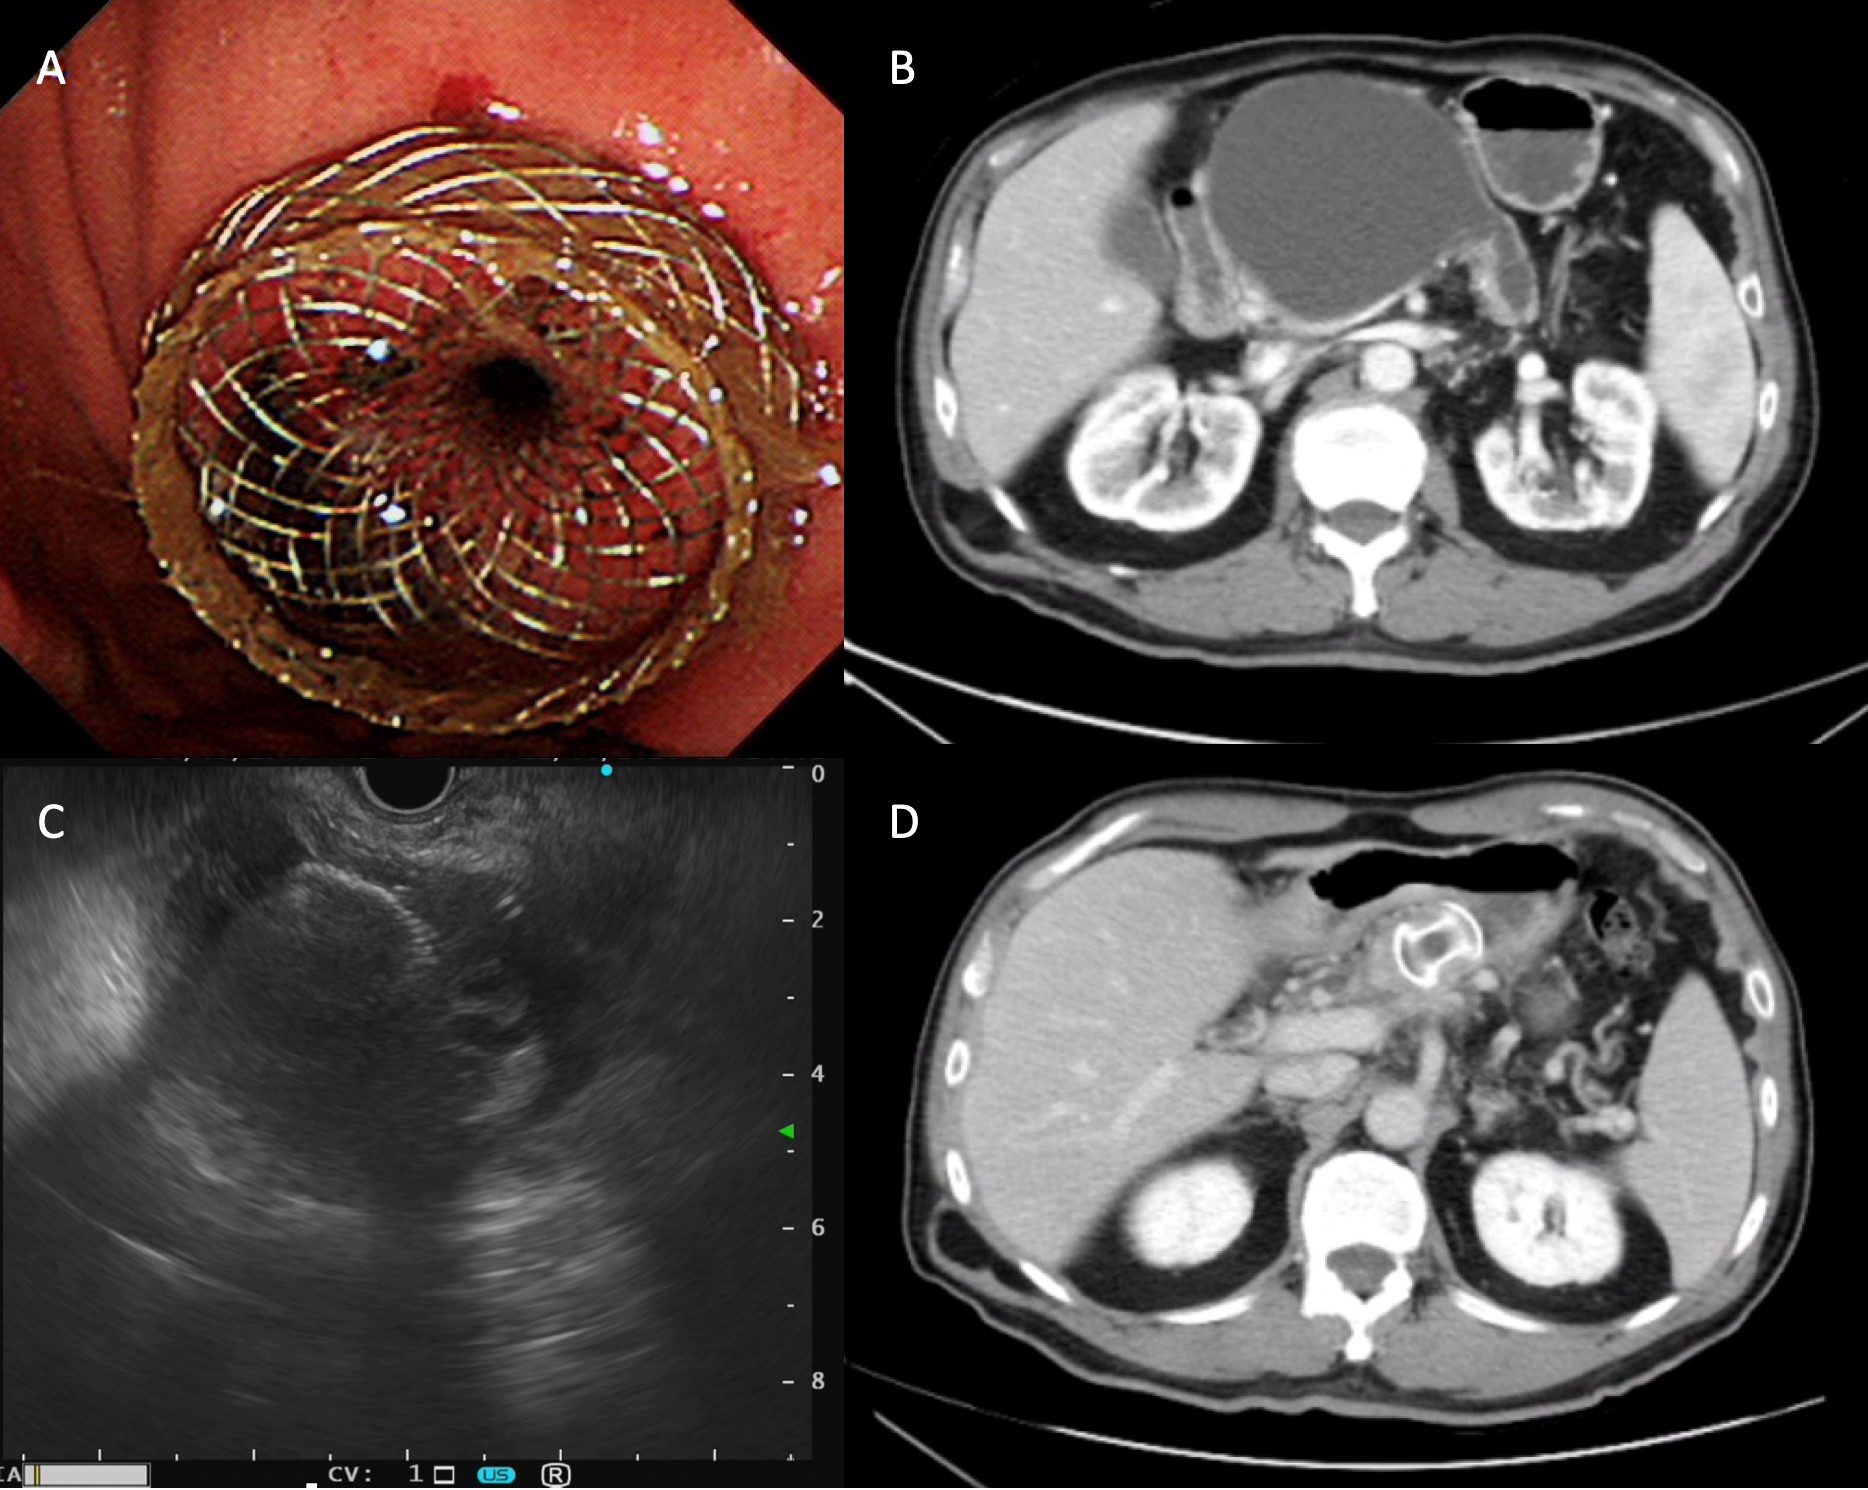

消化系| 特色介紹- 中國醫藥大學附設醫院